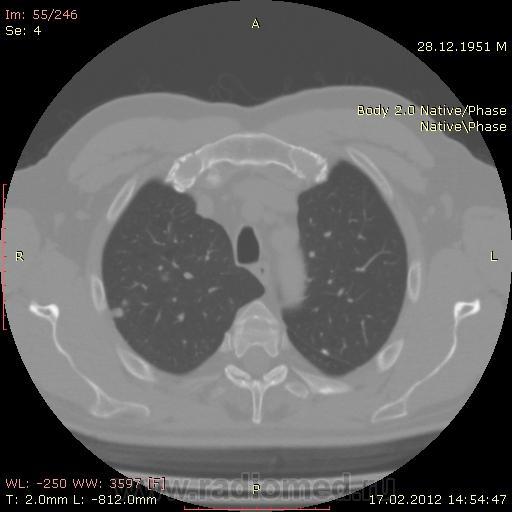

КТ.

В феврале 2012 года при очередном флюрографическом обследовании были обнаружены изменения в лёгких. По собственной инициативе было сделано КТ лёгких.